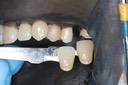

Joe Cha #29 pre-op

Joe Cha #29 prep

Joe Cha #29 die

Joe Cha #29 finish